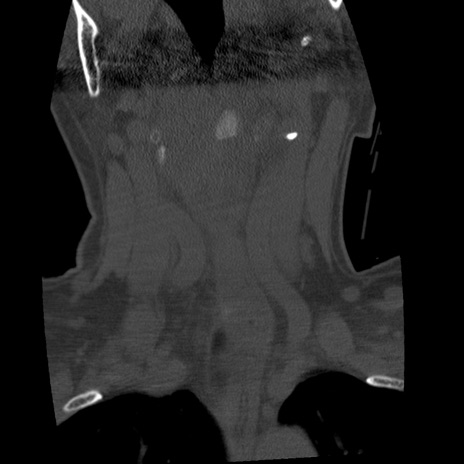

症例50 頚椎CT(冠状断像)

頚椎CT